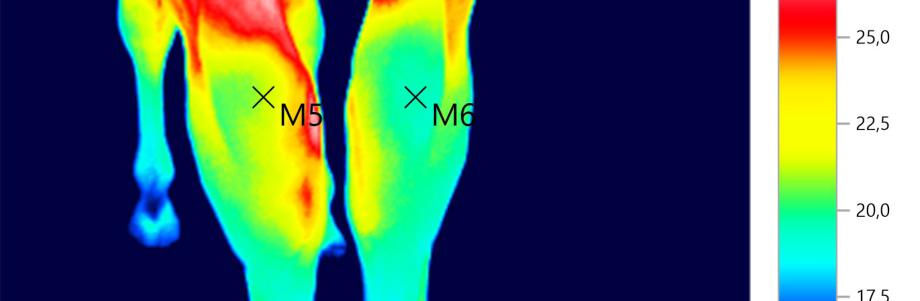

Jeder Körper mit einer Temperatur oberhalb des absoluten Nullpunktes sendet Wärmestrahlung/ Infrarot aus. Je höher die Strahlungsintensität, desto größer ist die Oberflächentemperatur. Es lässt sich mit Hilfe der Wärmebildkamera (Langestrahlen) eine bildliche Darstellung der Temperaturverteilung einfangen. Durch die bildliche Darstellung, ist es mir möglich thermische Auffälligkeiten zu analysieren. Im Rechts-/Linksvergleich fallen Thermische Differenzen auf, die Hilfe zur weiteren Diagnostik geben. Oder ein Warnhinweis ist, dass im Körper etwas nicht in Harmonie ist. Doch nicht nur diagnostisch hilft die Infraroterfassung. Auch das Training kann nach einem Screening optimiert werden, da der Reiter dann erfährt, wie lange sein Tier braucht, bis es „aufgewärmt“ ist. Sitzt der Reiter nicht im Lot, oder klemmt der Sattel, so wird auch dies durch unterschiedliche Farbschattierungen (Hot- & Coldspots) sichtbar. Allerdings kann nur oberflächlich eine Orientierung gegeben werden. Organe können nicht abgebildet werden.

Die Temperaturunterschiede bzw. Auffälligkeiten geben Hinweise geben auf:

ungeklärte Lahmheiten / entzündliche Prozesse / Sehnen & Muskelverletzungen / Arthrose -Arthritis im Akutstadium / Kissing Spines / Hufgeschwür / Rehe/ Zahnproblematiken / Durchblutungsstörungen durch z.B. Blockaden /Uvm